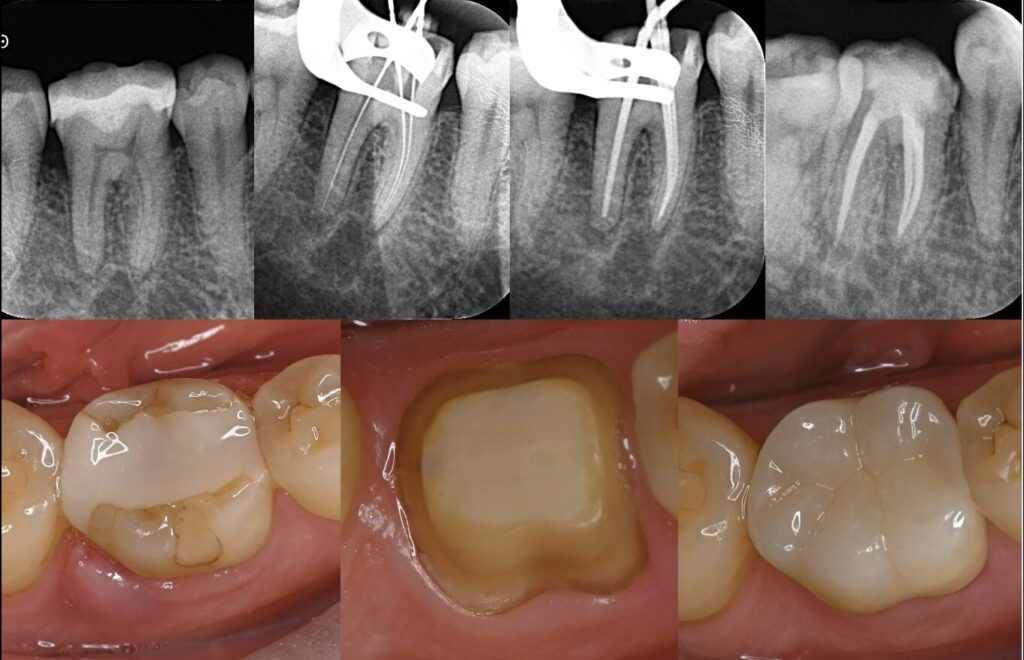

First, lets understand what root canal treatment is. Simply put, its a dental procedure performed when the tooths pulp—comprising nerves and blood vessels—gets inflamed or necrotic. The dentist cleans out the diseased tissue and seals the space with fillings to prevent bacterial re-entry. Specialized instruments are used to reach deep into the tooth roots, leading many to think their teeth are "hollowed out," raising concerns about stability.

The truth is, root canal treatments themselves dont directly cause teeth to loosen. However, because the tooth was already infected or damaged before treatment, its structure might have weakened. Without proper follow-up care like a protective crown, pressure during chewing can concentrate on the remaining tooth structure. Over time, this can lead to cracks or even a sensation of looseness.

Getting a root canal treatment in the Mainland is fundamentally the same as having it done in Hong Kong, with similar techniques employed. Many mainland dentists recommend swiftly adding a crown after completing root canal therapy. This crucial step enhances durability and reduces the risk of fractures over time. If youre heading north for treatment, make sure to discuss follow-up repair pla

ns with your dentist.